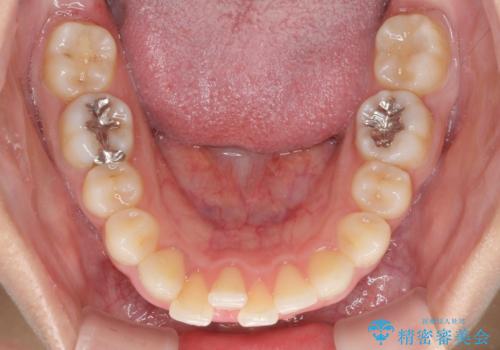

- 以前の矯正治療の後戻りを気にして来院された患者様です。

下顎前歯にデコボコがあるため、ワイヤー矯正により改善することとしました。